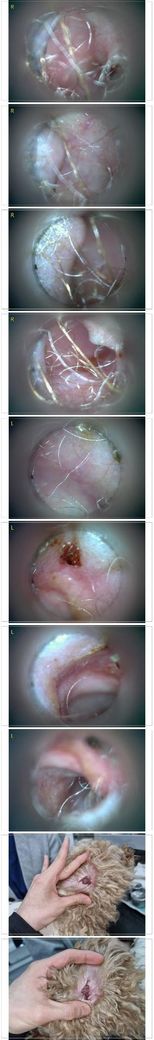

사진만 보고 확진할 수는 없지만 지금 올려주신 귀는 적어도 오른쪽은 정상으로 보이기 어렵습니다 왼쪽은 비교적 연분홍에 가까워 보이지만 오른쪽은 털과 분비물이 많이 차 있고 피부가 자극받은 듯한 모습이라 외이염 가능성을 먼저 생각하게 됩니다 그리고 질문자님이 적어주신 머리 털기 하루 여러 번 귀 만질 때 통증 솜만 닿아도 예민함 귀 긁기 같은 증상은 외이염에서 흔한 신호입니다

다만 이 사진만으로 중이염이나 내이염이라고 단정할 수는 없습니다 중이염이나 내이염은 귀 통증과 머리 털기만으로도 올 수 있지만 보통은 고개 기울어짐 비틀거림 안구가 흔들리는 증상 얼굴 한쪽 처짐 같은 더 깊은 신경 증상이 같이 보일 때 더 의심합니다 지금 적어주신 내용만 보면 제일 먼저는 오른쪽 외이도 염증과 통증 조절이 우선으로 보입니다